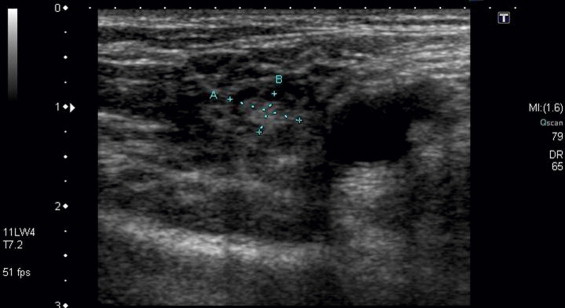

When the VGLN flap is indicated for transfer for the treatment of upper limb lymphedema, the available quantity of lymph nodes in the groin area is one of the most important factors predicting success. Duplex ultrasonography can be used to detect sizable (greater than 0.5 mm in diameter) lymph nodes ( Figure 14.5 ) or an MRI can be used to completely survey the groin lymph nodes in great detail. Duplex ultrasonography is a cheap, easy, and less time consuming (30 minutes) imaging modality. The MRI is more accurate, expensive, and is more time consuming (3–4 hours). Once the quantity and location of available lymph nodes is confirmed, the groin site may be chosen and flap design can be made accordingly.